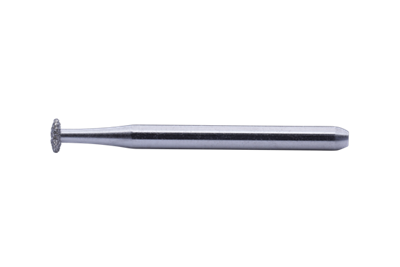

LIFE SAVER BUR (PK5)

LIFE SAVER BUR (PK5)

PRODUCT DETAILS

- A special design to clean any excessive adhesive under the wings without damage the brackets. (when used properly with light force).

- May be used with SS and ceramic brackets.

- Always use light force to remove the extra adhesive.